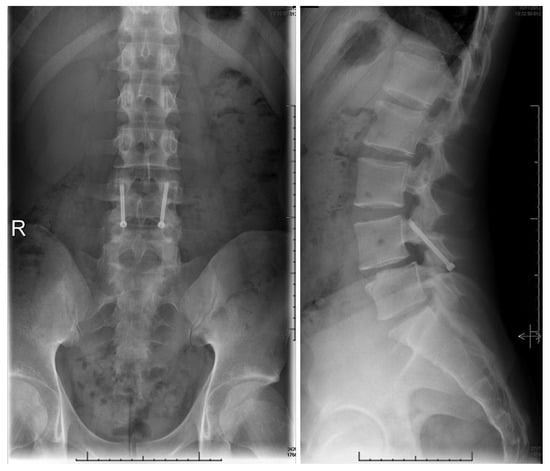

1.9.4. Pedicle Screw Based Repairs

- Tokuhashi, Y.; Matsuzaki, H. Repair of defects in spondylolysis by segmental pedicular screw hook fixation. A preliminary report. Spine 1996, 21, 2041–2045. [Google Scholar] [CrossRef] [PubMed]

- Debusscher, F.; Troussel, S. Direct repair of defects in lumbar spondylolysis with a new pedicle screw hook fixation: Clinical, functional and Ct-assessed study. Eur. Spine J. 2007, 16, 1650–1658. [Google Scholar] [CrossRef] [PubMed]

- Kakiuchi, M. Repair of the defect in spondylolysis. Durable fixation with pedicle screws and laminar hooks. J. Bone Jt. Surg. 1997, 79, 818–825. [Google Scholar] [CrossRef]

- Gao, Y.; Zhao, C.; Luo, L.; Liu, L.; Liang, L.; Jiang, D.; Li, P.; Zhou, Q. Surgical Reduction and Direct Repair Using Pedicle Screw-Rod-Hook Fixation in Adult Patients with Low-Grade Isthmic Spondylolisthesis. Pain Res. Manag. 2022, 2022, 8410519. [Google Scholar] [CrossRef]